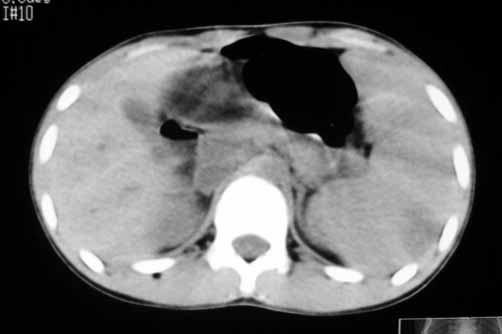

以下是引用zhangzhongshou在2007-5-22 21:04:00的发言:[br]1、脾肿大[br]2、脾脏低密度影,血管瘤?脾梗塞不能除外,建议增强扫描。

以下是引用dyqct在2007-5-22 20:45:00的发言:[br]巨脾,可疑梗塞,建议增强、查血象进一步检查

以下是引用liuyue在2007-5-23 7:57:00的发言:[br]腹主动脉周多个肿大淋巴结,脾大伴三角形低密度影,肠腔积气,考虑:1淋巴瘤2脾大伴梗塞3肠腔积气(肿大淋巴结压迫所致)